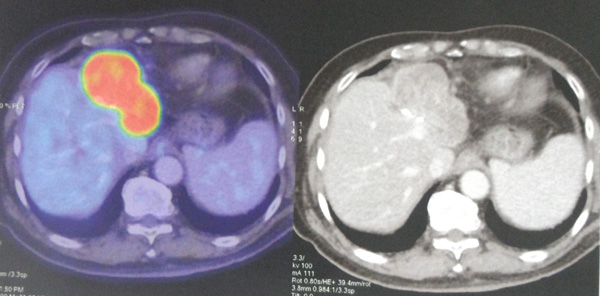

Unfortunately this euphoria did not last long. Six months later (i.e. about 9 months after the surgery) another PET /CT scan on 11 March 2013, revealed a new recurrent hetergenous hypodense mass in the liver at the resected margin measuring 8.0 x 4.8 cm (picture below).

11-Mar-13-recurrence

11 March 2013 TEN MONTHS: Interval development of an intensively hypermetabolic measuring 8.0 x 4.8 cm at the hepatic resection site consistent with recurrent disease.

11 March 2013. The liver tumour recurred and grew to 8 cm in size (initial size was 3 cm)